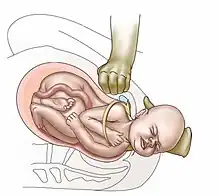

Suprapubic pressure being used in a shoulder dystocia

• Anterior shoulder disimpaction (suprapubic pressure);[11]

• McRoberts maneuver;[15][16] involves hyperflexing the mother's legs tightly to her abdomen. This widens the pelvis, and flattens the spine in the lower back (lumbar spine). If this maneuver does not succeed, an assistant applies pressure on the lower abdomen (suprapubic pressure), and the delivered head is also gently pulled. The technique is effective in about 42% of cases;

• Suprapubic pressure (or Rubin I);[17]